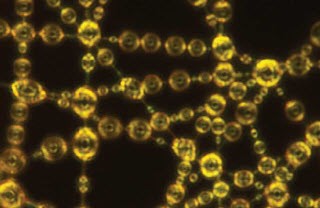

Opening the blood-brain barrier allows the body to remove plaque in the hippocampus